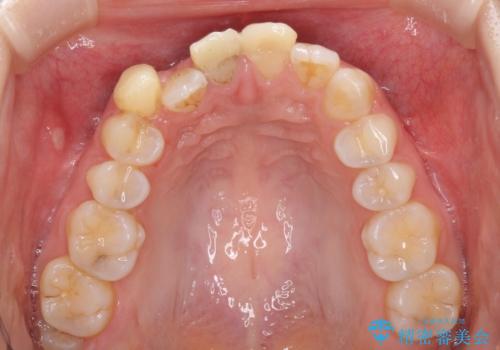

- 転倒により前歯の一部が欠けてしまったとのことで来院された患者様です。

神経が保存できる歯、神経を除去しなければならない歯、抜歯が必要な歯があり、ブリッジやインプラントなどによる治療を提案しました。

元々歯並びが気になっていたとのことで、前歯の治療を行うことを契機に矯正治療も行うこととしました。

本来であれば積極的に小臼歯を抜歯して口元を下げても良いのですが、前歯を1本抜歯しないといけなくなったため、非抜歯矯正をインビザラインを用いて行うこととしました。

補助装置により上顎歯列を遠心移動させたため、非抜歯でしたが口元の突出感をある程度改善させることができました。

欠けてしまった前歯もオールセラミッククラウンにて自然に補綴することができました。